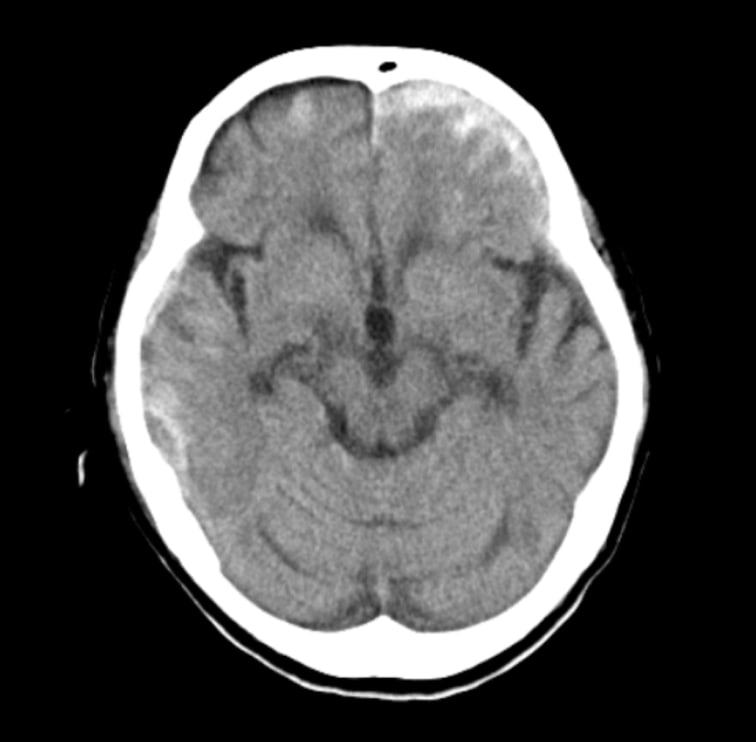

- CT画像情報から頭蓋内の高吸収・低吸収領域を抽出

頭部単純CTの画像情報から頭蓋内の高吸収・低吸収領域を抽出し強調表示をします

- 頭部単純CTの画像情報から頭蓋内の高吸収・低吸収領域を抽出し強調表示をします

- 頭蓋内で前後のスライス及び同一スライス内の左右で比較して組織構造もしくは組織境界の不明瞭化が見られる領域を表示します

- 抽出領域がセグメンテーション表示されることで視覚的な確認が可能です